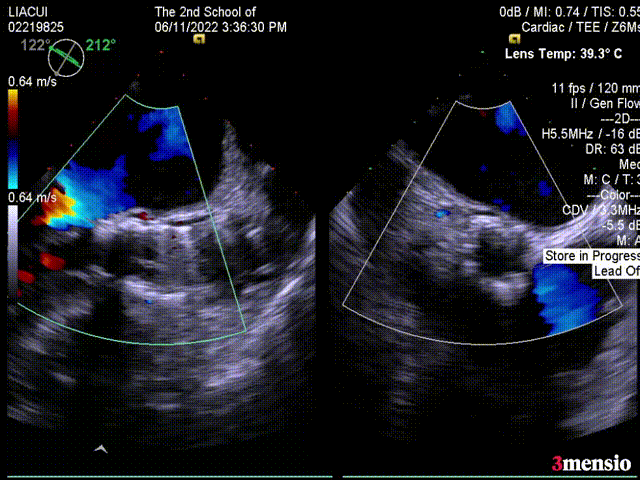

术前超声压差评估:

术前超声显示压差121mmHg